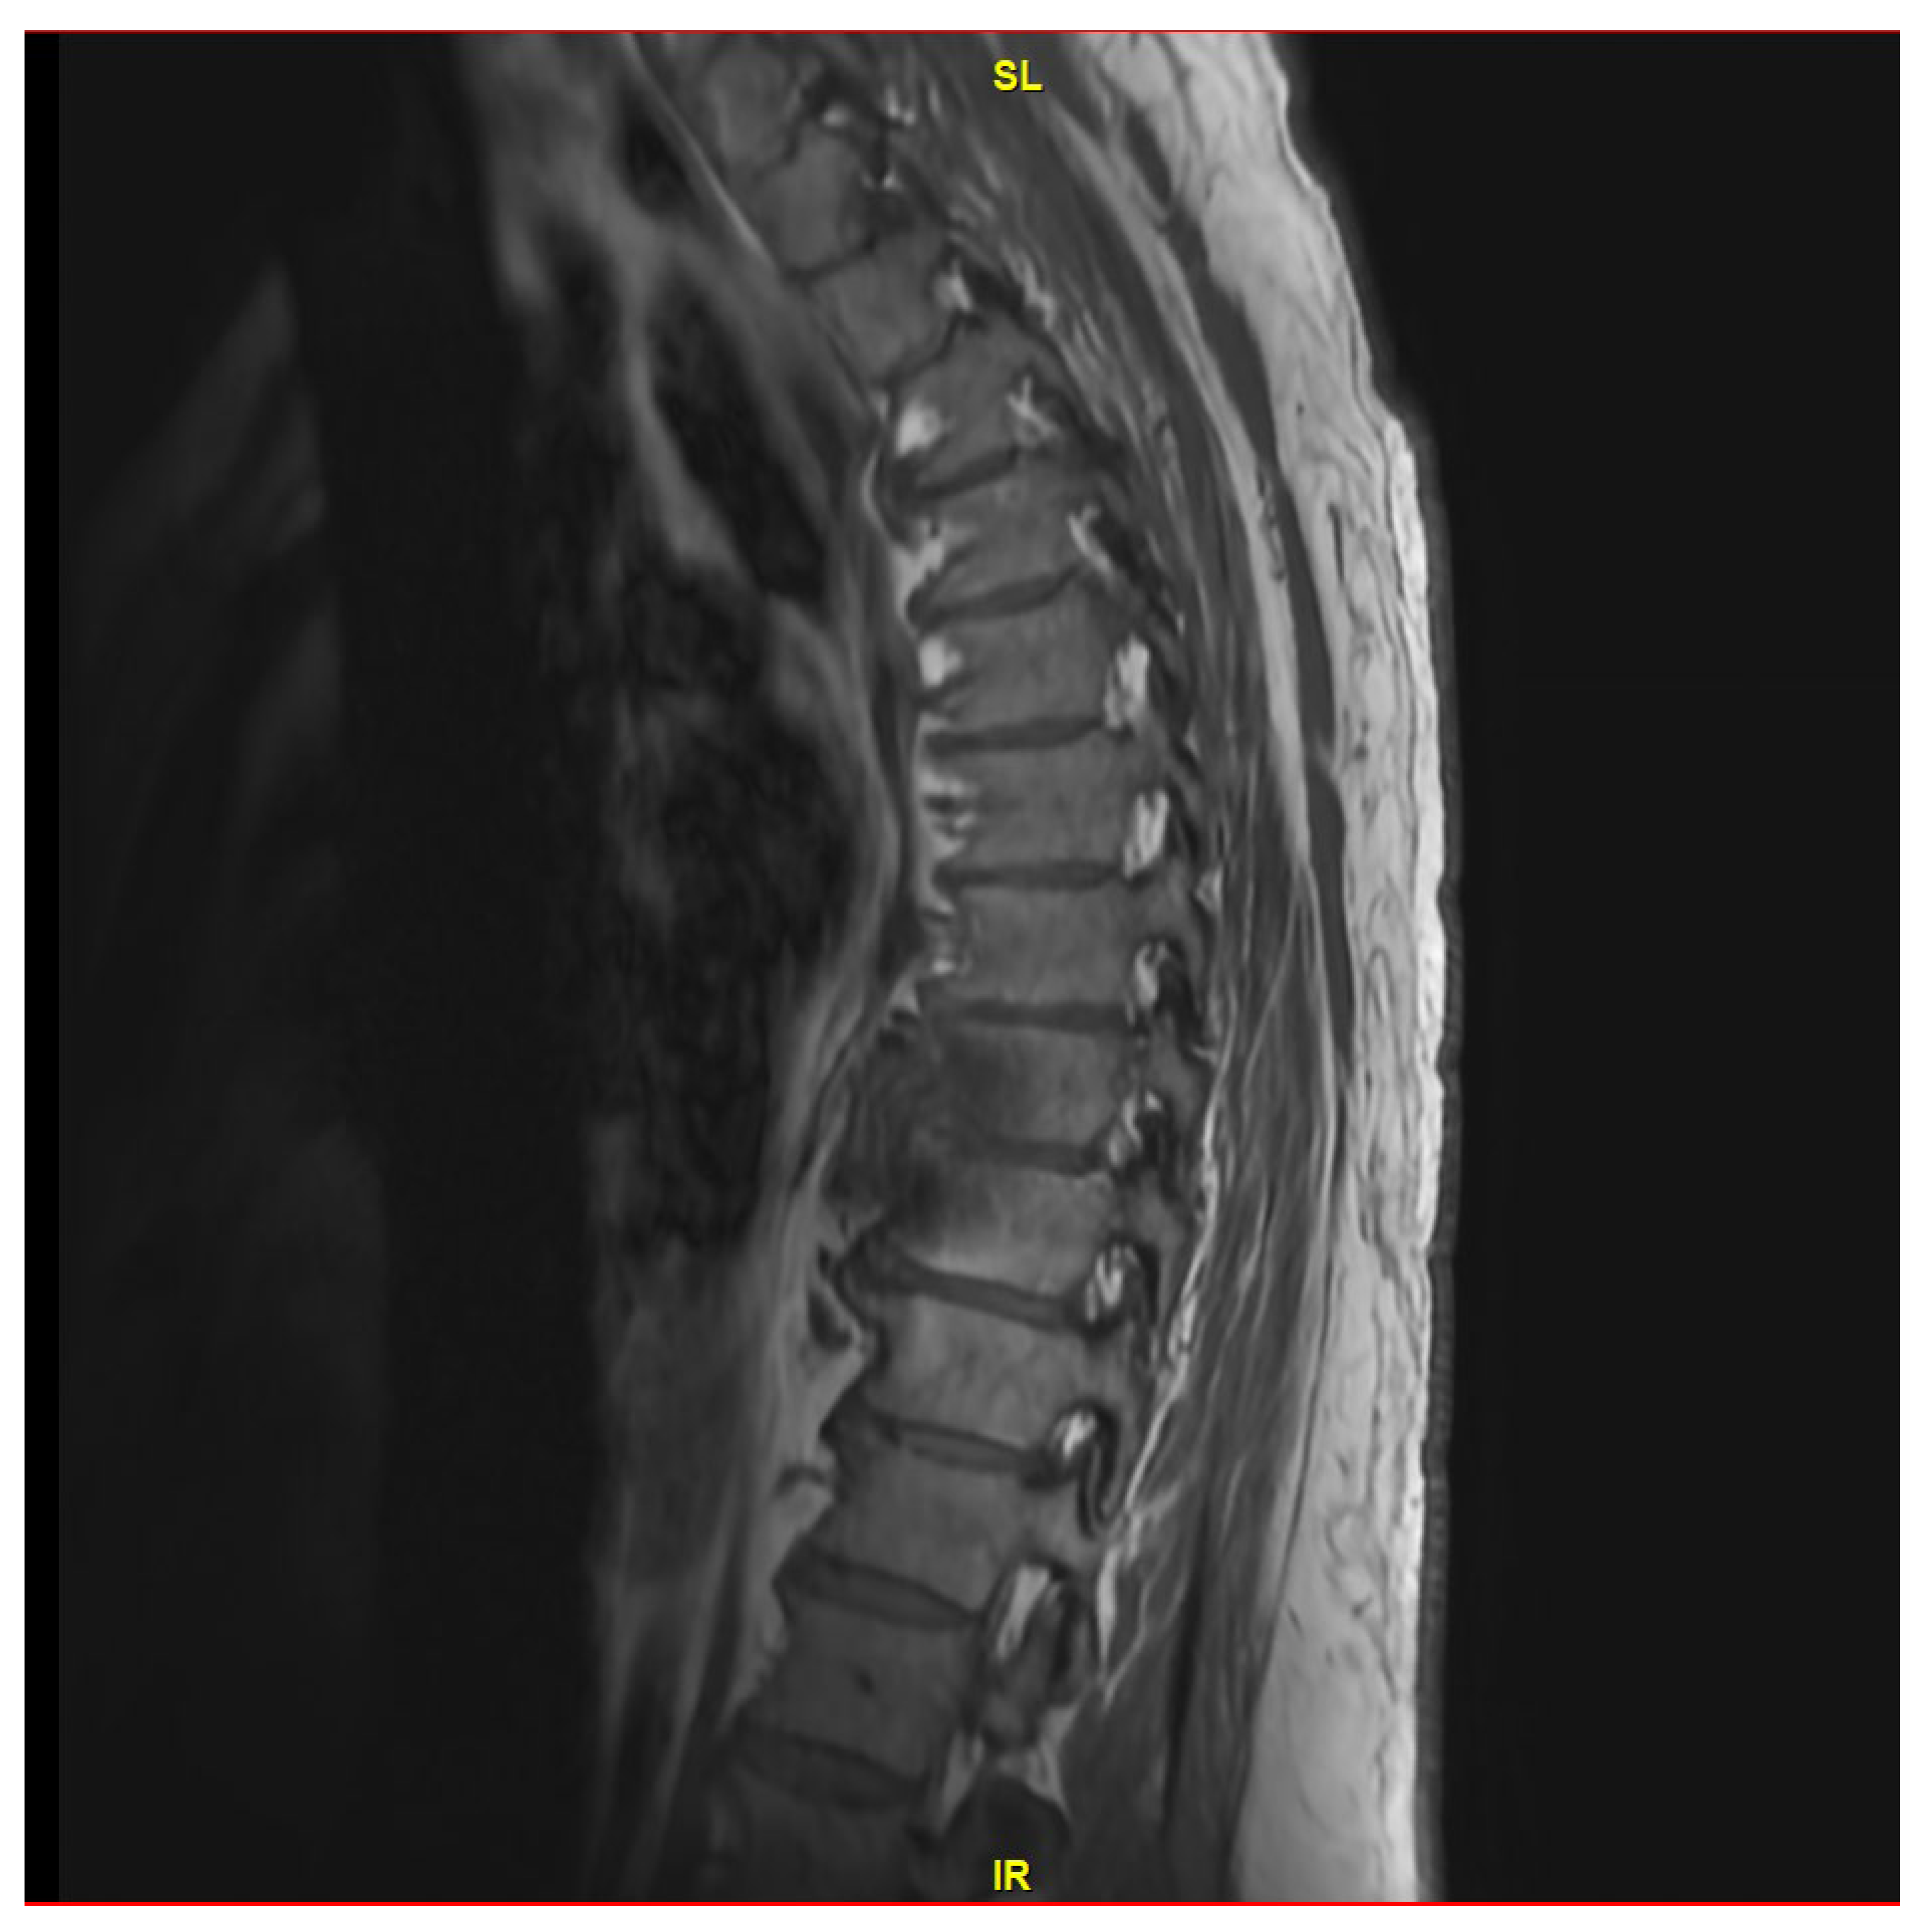

He demonstrated progressive improvement in his pain on ceftriaxone without the need for narcotic analgesics. He underwent a third MRI after 6 weeks of treatment (on 29 August 2023), which showed the known changes at T8 and T9, with near resolution of the fluid within the T8-T9 disc (Figure 2). Due to improvement but continued destructive changes and edema, the decision was made to pursue oral therapy after completion of IV ceftriaxone with oral cefuroxime 500 mg q.12 h, which was initiated on 14 September 2023.

He was evaluated by Neurosurgery on 27 September 2023, and they felt the final recommendations for surgical removal of his hardware were not indicated at this time. He followed up with infectious diseases again on 11 December 2023 after undergoing a repeat MRI of the thoracic spine on December 8th, demonstrating complete resolution of the T8-T9 disc space infection (Figure 3). At that time, the patient reported no back pain and was not requiring pain medication. Considering his L5-S1 spinal fusion hardware, he continued his suppressive oral cefuroxime.

Figure 2. MRI thoracic spine with and without IV contrast revealing redemonstration of T8-T9 diskitis with mild improvement of paraspinal/epidural phlegmon.

Figure 3. MRI thoracic spine with and without IV contrast showing a completely resolved T8-T9 disc space infection.